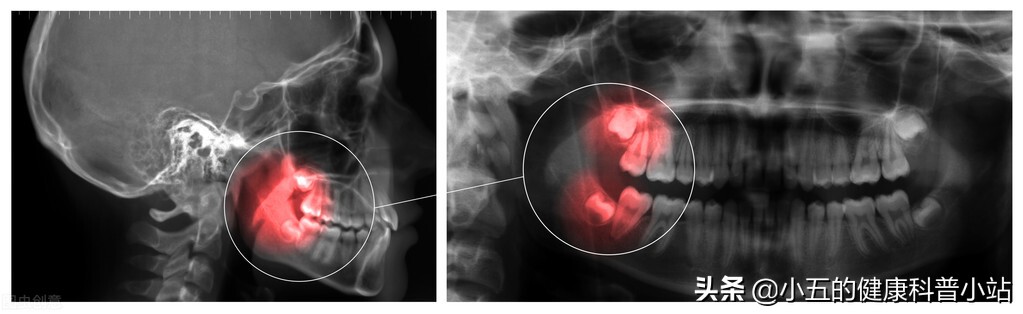

有部分人的智齿并不是老老实实地长在最后,而是张在其他牙齿的附近,造成对其他牙齿的挤压,导致整个牙齿序列歪斜。 更可恶的是这种智齿往往并不长出牙床,所以表面上看是看不出的,需要牙医拍了X光才能诊断 ,这种智齿侵犯邻牙的情况会导致患者在 咀嚼的时候非常不舒服,甚至造成严重的牙痛 。